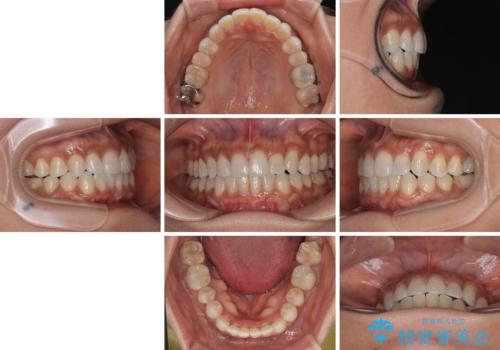

咬合力による臼歯離開は顎間ゴムで改善されましたが、それとは別に下顎小臼歯がマウスピースに追従せず、補正のためのゴムかけが必要となりました。

大変なゴムかけ作業を頑張っていただき、無事に治療を終えることができました。

クロスバイトを治したい インビザラインによる矯正治療